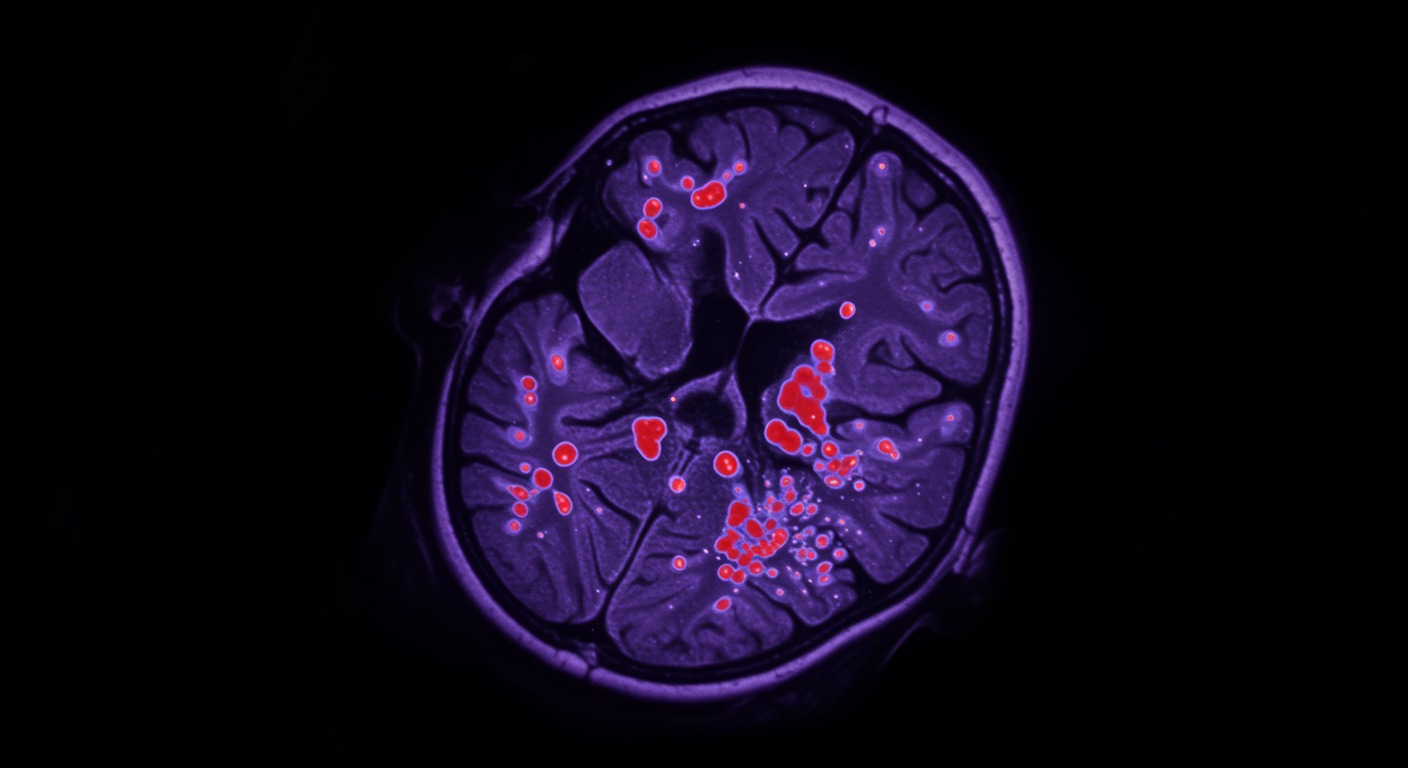

Sawtooth waves are distinctive brain wave patterns that occur during REM sleep, characterized by their sharp, serrated appearance on EEG recordings. This advanced neuroimaging research reveals that these waves are associated with widespread brain activation across multiple regions, providing crucial insights into how the brain generates dreams and processes memories during REM sleep. The waves appear to coordinate neural activity across distant brain regions, facilitating the complex cognitive processes that occur during our most vivid dreaming periods.

Advanced neuroimaging studies using simultaneous EEG-fMRI have revealed that sawtooth waves during REM sleep are associated with activation in multiple brain regions including the visual cortex, motor areas, limbic structures, and prefrontal regions. This widespread activation pattern is remarkably similar to the brain activity seen during complex waking cognitive tasks, despite the fact that the person is deeply asleep and dreaming.

Sawtooth waves during REM sleep are associated with widespread brain activation involving visual, motor, emotional, and executive brain regions. This activation pattern explains why dreams can be so vivid, emotionally intense, and cognitively complex despite occurring during sleep. The waves appear to facilitate the integration of different types of information—visual imagery, emotions, memories, and motor experiences—that characterizes dream content.